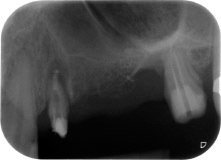

Abb. 1: Bei einer 58-jährigen Patientin zeigt die Röntgenaufnahme vor der OP eine apikale Parodontalläsion an Zahn 24 und einen horizontalen Knochenabbau im zweiten Quadranten.

Eine 58-jährige Patientin, die auch eine gute Freundin und ärztliche Kollegin ist, beschwerte sich über Schmerzen und erhöhte Beweglichkeit ihres Brückenpfeilers 24. Es lag auch eine parodontale Entzündung vor, mit Taschentiefen von 7 mm mesiobukkal und mehr als 12 mm distal und einer Furkationsbeteiligung dritten Grades. Darüber hinaus zeigte die Röntgenaufnahme eine großflächige apikale Aufhellung am endodontisch (alio loco) vorbehandelten Zahn 24 (Abb. 1).

Ein Jahr zuvor waren die Zähne 25 und 26 vor dem Einsetzen der Brücke aufgrund traumatischer und endoparodontaler Ursachen extrahiert worden. Eine Paro-Endo-Läsion wurde bei unklarer ätiologischer Hauptkomponente für den Zahn 24 diagnostiziert. Die Patientin machte deutlich, dass sie ihre Pfeilerzähne 24 und 27 behalten und keinen endgültigen oder temporären herausnehmbaren Zahnersatz akzeptieren will. Darum wurde vereinbart, alles zu versuchen, beide Zähne, trotz der nach den radiologischen und klinischen Befunden als schlecht einzustufenden Prognose, zu erhalten.